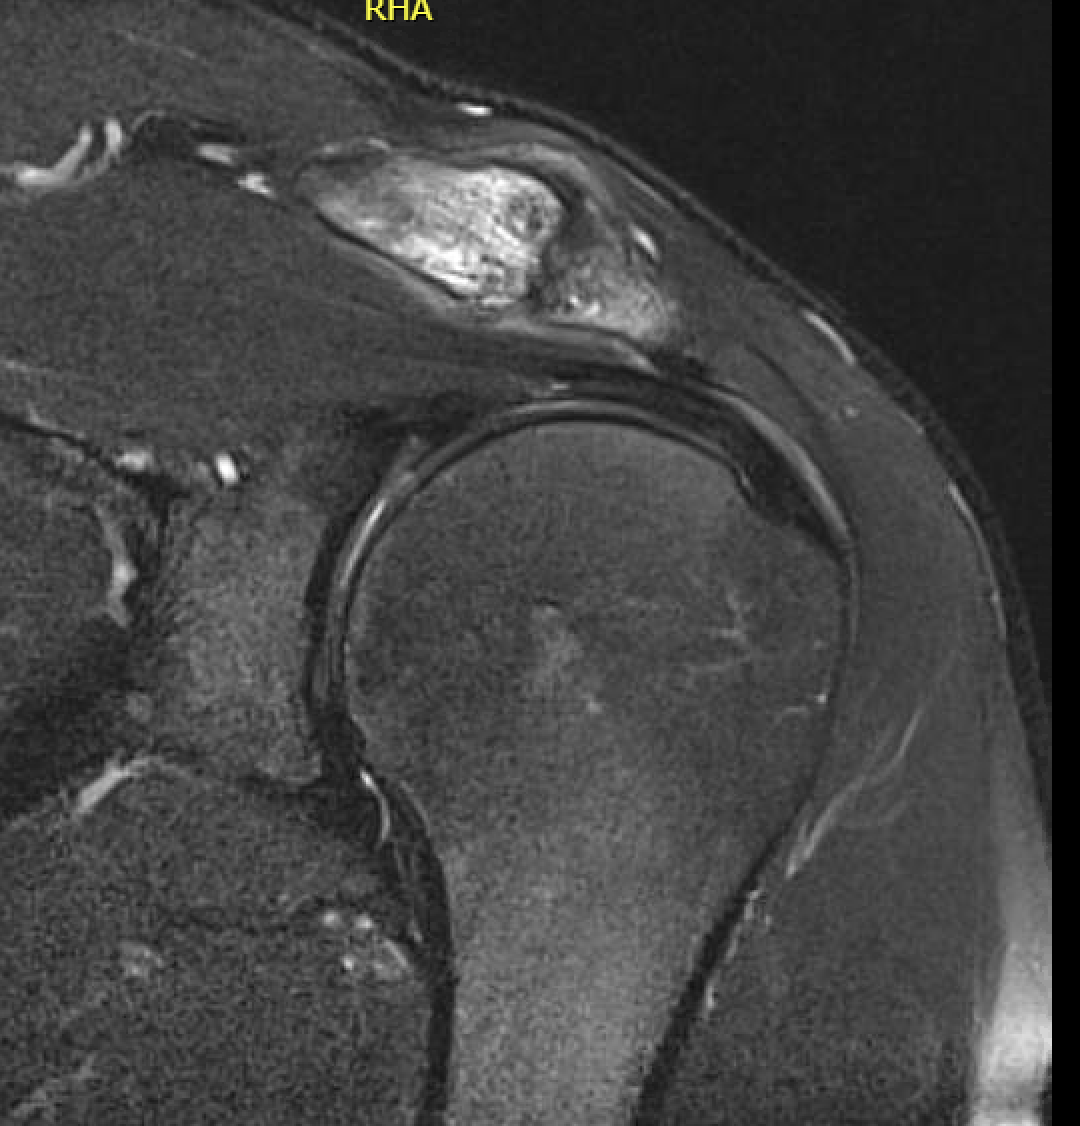

MRI

Acromioclavicular osteoarthritis

Stein et al. J Should Elbow Surg 2001

Grade I: Normal

Grade II: Capsular distension, bone marrow edema, mild joint narrowing

Grade III: Capsular distension, joint space narrowing, marginal osteophytes

Grade IV: Markedly abnormal ACJ with large osteophytes

Acromioclavicular joint osteolysis